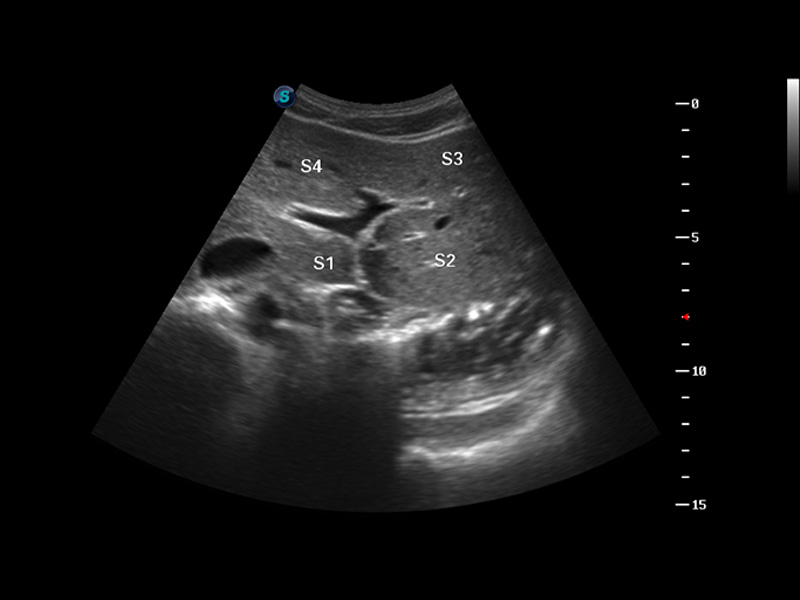

S8 EXP便携式彩色多普勒超声诊断仪是银河优越会研发的高端全身应用型便携彩超。高通道的VIS平台融合可视化(Visual)、智能化(Intelligent)和人性化(Smart)的特点,配以银河优越会自主研发生产的探头大家族,使您能够快速、准确的获得病人信息,提高工作效率的同时减轻疲劳。

成像技术

3D/4D成像